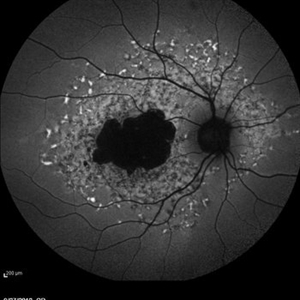

Late Stage Stargardt's Disease Late Stage Stargardt's DiseaseMar 13 2013 by Hamid Ahmadieh, MD Autofluorescence imaging of the right eye of a 46-year-old man with decreased VA due to advanced Stargardt's disease. Photographer: Nayereh Hadipoor, Negah Eye Center, Tehran Imaging device: Heidelberg Spectralis Condition/keywords: autofluorescence imaging, Stargardt disease

Late Stage Stargardt's Disease Late Stage Stargardt's DiseaseMar 13 2013 by Hamid Ahmadieh, MD Autofluorescence imaging of the left eye of a 46-year-old man with decreased VA due to advanced Stargardt's disease. Photographer: Nayereh Hadipoor, Negah Eye Center, Tehran Imaging device: Heidelberg Spectralis Condition/keywords: autofluorescence imaging, Stargardt disease